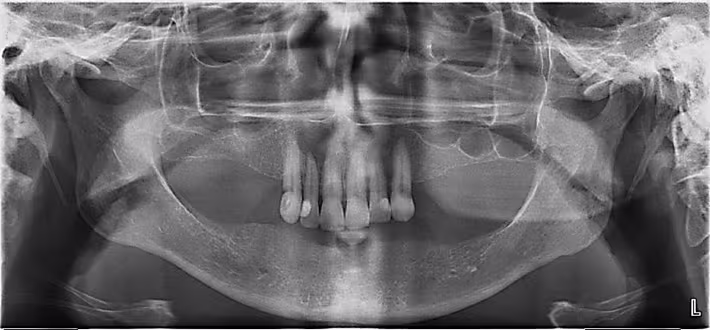

Figure 21. Optimal Panoramic Image.

In reality, most panoramic images are not optimal nor ideal but rather present with minor yet acceptable error(s) that do not interfere with diagnosis and treatment planning. In such instances, a retake is not justified.